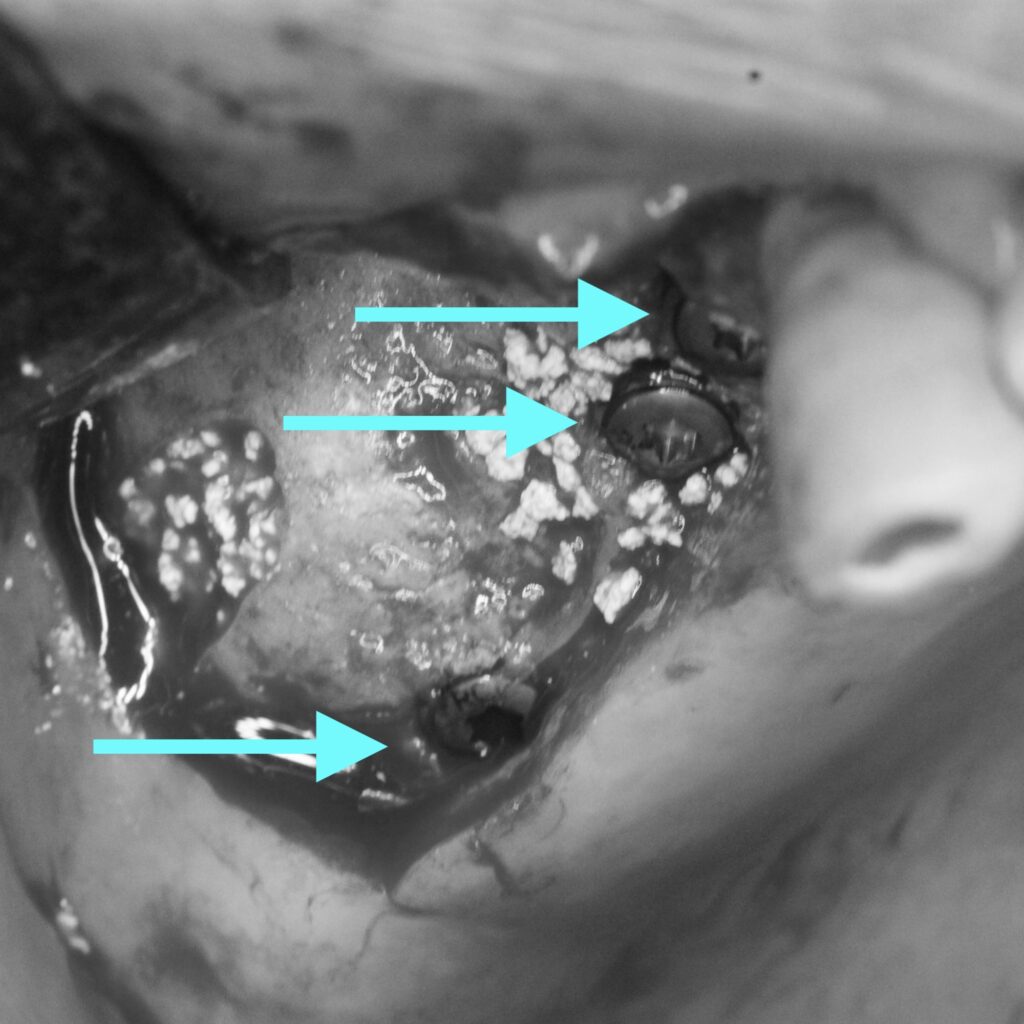

今後インプラントの処置を行い、左右で同じように噛めるよう進めていく事になりました。